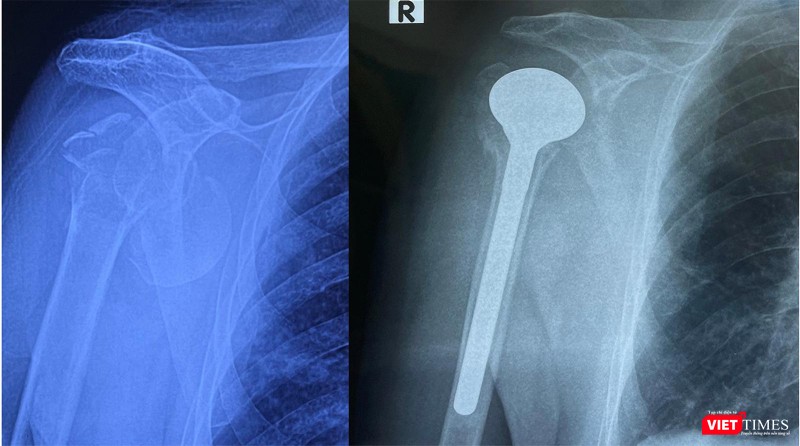

Tại Bệnh viện Hữu nghị Việt Đức, bệnh nhân đã được các bác sĩ Khoa Phẫu thuật Chi trên và Y học thể thao thăm khám và chẩn đoán bị gãy cổ xương cánh tay làm nhiều mảnh kèm theo trật khớp nên không thể đưa đinh nẹp vào kết hợp xương.

Sau khi hội chẩn liên chuyên khoa Tim mạch, Gây mê hồi sức, Chấn thương chỉnh hình, ThS.BS Lưu Danh Huy - Phó Trưởng khoa Phẫu thuật Chi trên và Y học thể thao – Bệnh viện Hữu nghị Việt Đức - đã quyết định thay khớp vai bán phần cho người bệnh.

ThS.BS Lưu Danh Huy cho biết, đây là ca bệnh hy hữu, bệnh nhân là người cao tuổi nhất Việt Nam được thay khớp vai bán phần. Ở bệnh nhân cao tuổi với những bệnh lý nền như đái tháo đường, cao huyết áp, bệnh lý mạch vành sẽ rất nhiều nguy cơ tai biến trong phẫu thuật. Bên cạnh đó, đối với những bệnh nhân cao tuổi xương loãng thì nguy cơ gãy xương khi đưa dụng cụ phẫu thuật vào rất cao, cũng như có sốc phản vệ đối với xi măng gắn dụng cụ vào xương, tử vong ngay trên bàn mổ.

Sau hơn 1 tiếng đồng hồ thực hiện, ca phẫu thuật hy hữu đã diễn ra thành công. Sau mổ tình trạng bệnh nhân ổn định, tiếp tục được theo dõi, tập phục hồi chức năng 24h sau mổ và xuất viện sau 5 ngày phẫu thuật.